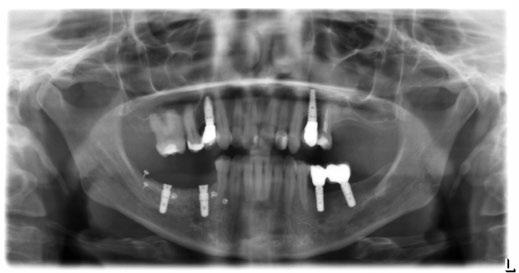

-Estudio radiográfico inicial (ortopantomografía y radiografías periapicales) (Figura 2).

Figura 2. Ortopantomografía inicial.

25, 26, 28, 37, 38, 47 y 48. Presentaba corona desajustada en 13 con extensión en 12, implantes en 35-36, 45-46, con coronas ferulizadas en 35-36, 45-46, y dientes anteriores superiores con enfermedad periodontal Grado IV.

3. Exploración de tejidos duros

En la exploración radiográfica (OPG, CBCT) observamos la existencia de pérdida ósea interproximal, lesión apical a nivel de la raíz mesial del 27 y el cordal del primer cuadrante incluido y neumatización sinusal del primer y segundo cuadrante.

En el CBCT observamos pérdida ósea posterior superior debida a la neumatización de los senos maxilares izquierdo y derecho. También podemos observar disponibilidad ósea apical suficiente en dientes antero-superiores para la realización de una Implantología inmediata y corticales vestibulares y palatinas conservadas.